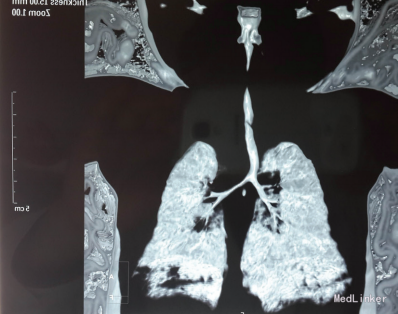

初步诊断:①新生儿急性喉炎(Ⅳ度喉梗阻);②新生儿肺炎;③新生儿腹泻病;④高血糖症。患儿入院后经皮氧饱和度为60%~80%。予小面罩0.5 L/min吸氧后发绀缓解,血气分析示:pH值 7.34; 氧分压(PO2 )297 mmHg;二氧化碳分压(PCO2)40.2 mmHg;碱剩余(BE) −3.7 mmoL/L。予布地奈德0.5 mg雾化吸入后喉喘鸣好转。入院2 h后再次出现面色发绀、喉喘鸣,予吸痰后无好转,且患儿自主呼吸弱,6~8次/min,不规则,有呼吸暂停,梗阻样吸气,立即直接喉镜挑起会厌软骨后喉喘鸣消失,呼吸困难、发绀很快缓解,予气管插管,喉镜下见喉部充血明显,会厌软骨宽大向上蜷曲,声门裂未见异常。患儿插管顺利,气囊加压给氧两侧呼吸音对称,予机械通气治疗。急诊头颅CT未见出血等异常。胸片及肺部CT均见斑片状实变影。患儿经机械通气24 h、肠外营养支持、补充维生素AD及钙剂等治疗10 d后病情好转,吃奶、精神、反应等基本情况稳定,呼吸平稳,肺部听诊可闻及少许喘鸣音。期间耳鼻喉科医师会诊除考虑会厌软骨太过宽大、向上蜷曲外,排除喉蹼、囊肿、息肉。出院前行胸部X线未见明显异常;超声心动图检查示三尖瓣少量反流,予出院。

出院后5 d患儿再次因吸气性喉梗阻、发绀就诊,予急诊喉部CT,多平面重建后发现患儿声门下气道异常狭窄,三维重建后甚至见气道连续性中断,考虑为喉软化致吸气性梗阻,大气道塌陷所致。诊断为喉软化症,予雾化及抗炎治疗后病情很快缓解。建议转上级医院治疗。患儿上级医院继续保守治疗后出院,此后有反复发作,每次发作后予抗感染及布地奈德雾化处理后好转。目前患儿已6个月,喉喘鸣症状轻微。 讨论:喉软骨软化症是引起新生儿喉喘鸣最常见的原因,该病易导致吸入性肺炎、反复呼吸道感染,病程长,影响小儿营养,易致营养不良等。